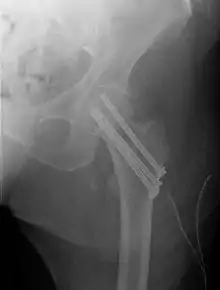

Closed reduction may not be satisfactory and open reduction then becomes necessary.[40] The use of open reduction has been reported as 8-13% among pertrochanteric fractures, and 52% among intertrochanteric fractures.[41] Both intertrochanteric and pertrochanteric fractures may be treated by a dynamic hip screw and plate, or an intramedullary rod.[40]

The fracture typically takes 3–6 months to heal. As it is only common in elderly, removal of the dynamic hip screw is usually not recommended to avoid unnecessary risk of second operation and the increased risk of re-fracture after implant removal. The most common cause for hip fractures in the elderly is osteoporosis; if this is the case, treatment of the osteoporosis can well reduce the risk of further fracture. Only young patients tend to consider having it removed; the implant may function as a stress riser, increasing the risk of a break if another accident occurs.